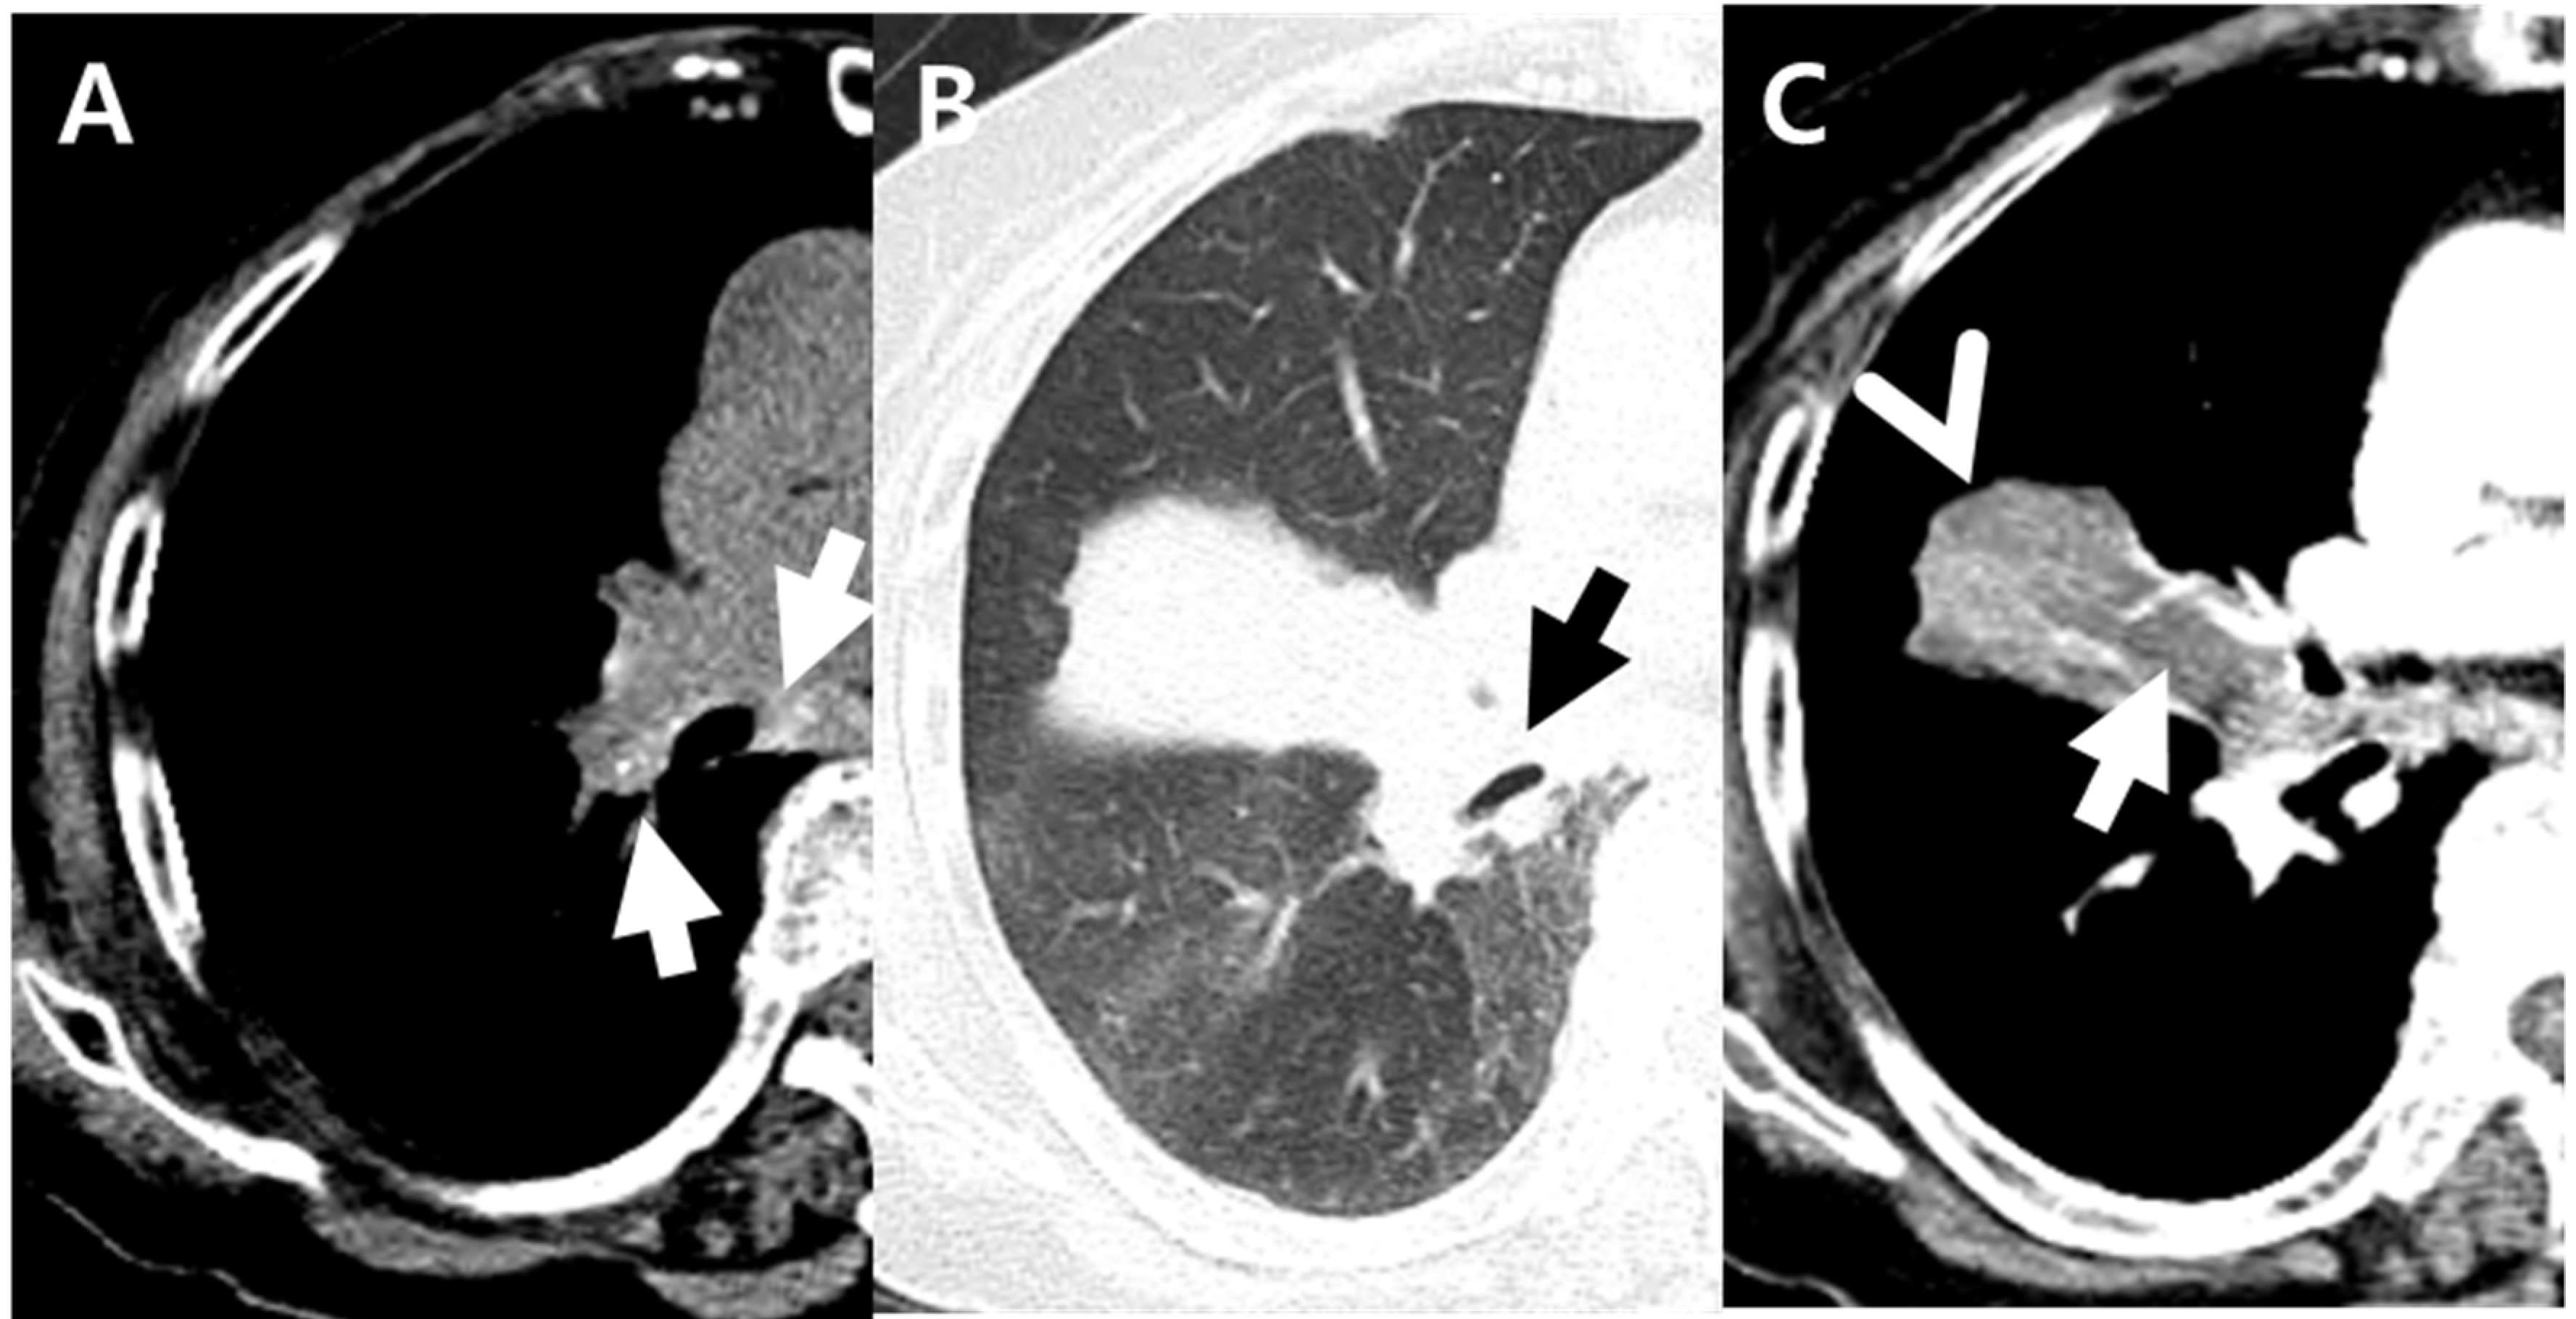

Figure 2.

An 87-year-old woman with pulmonary tuberculosis and underlying bronchial anthracofibrosis presented with dyspnea. (A,B) Non-enhanced axial CT scan showed tiny hyperdense foci (white arrows) within enlarged peribronchial and mediastinal nodes and complete obstruction (black arrow) of right middle lobar bronchus, resulting in atelectasis of right middle lobe. These CT findings suggested bronchial anthracofibrosis. (C) Contrast-enhanced axial CT scan showed focal contour bulge (arrowhead) and internal low-density area (arrow) within atelectasis. These findings were the only CT findings suggesting pulmonary tuberculosis in this patient. Culture of Mycobacterium tuberculosis and polymerase chain reaction test for Mycobacterium tuberculosis were positive from bronchial washes. CT = computued tomography.